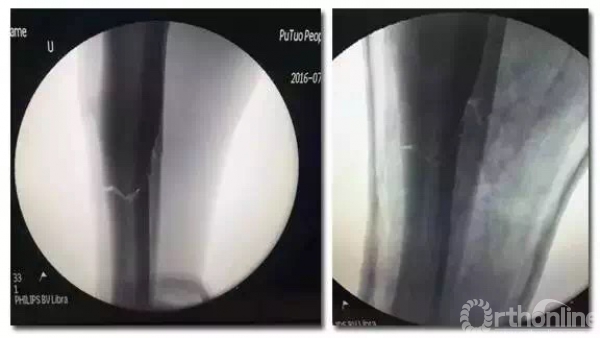

登巴·巴受伤当日,复旦大学附属华山医院及普陀区人民医院领导高度重视,华山医院夏军教授、陈文钧教授连夜赶往上海普陀区人民医院,与骨科主任陈舰共同完成全麻下手法复位,石膏固定。复位后X光片示效果满意,随后进行镇痛、消肿等对症治疗。

复位后x光片